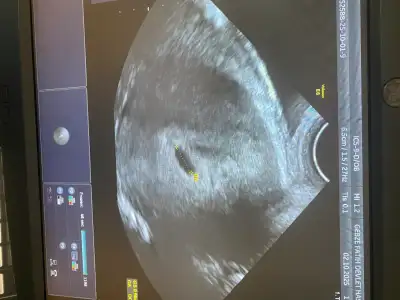

Benimkimde dün böyleydiİnşallah bu carsmaba gününün ultrason kağıdı bu gününkini almayı unuttum ama buna göre bariz büyümüştü

Şekli için bişey dediler miBenimkimde dün böyleydi

Benimki bariz yuvarlak ya farklı olması normal midir diye düşündümYok niye ki

Burda kaç haftalıktınız bende 4+6 da gideceğim yarın gözükür inşallahBenimkimde dün böyleydi

5+2ydiBurda kaç haftalıktınız bende 4+6 da gideceğim yarın gözükür inşallah